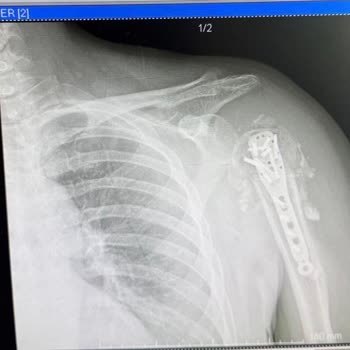

Yaklaşık 1,5 yıl önce geçirdiğim motosiklet kazası sonucu sol omzum kırıldığı için Marmaris’te bulunan Özel Ahu Hetman Hastanesi’ne başvurdum ve burada görev yapan A**** ve D**** isimli doktorlar tarafından ameliyat edildim. Ameliyat sonrasında beklenmeyen ciddi komplikasyonlar gelişti, enfeksiyon o...